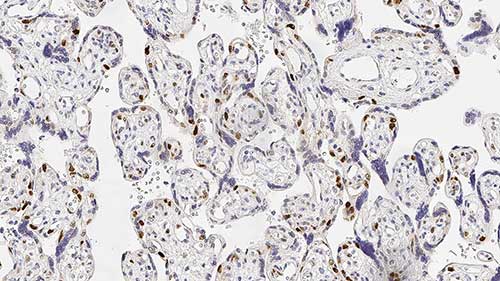

Human skin, Kaposi's sarcoma: immunohistochemical staining for HHV8. Note nuclear staining of neoplastic spindle cells. Human Herpesvirus 8: clone 13B10